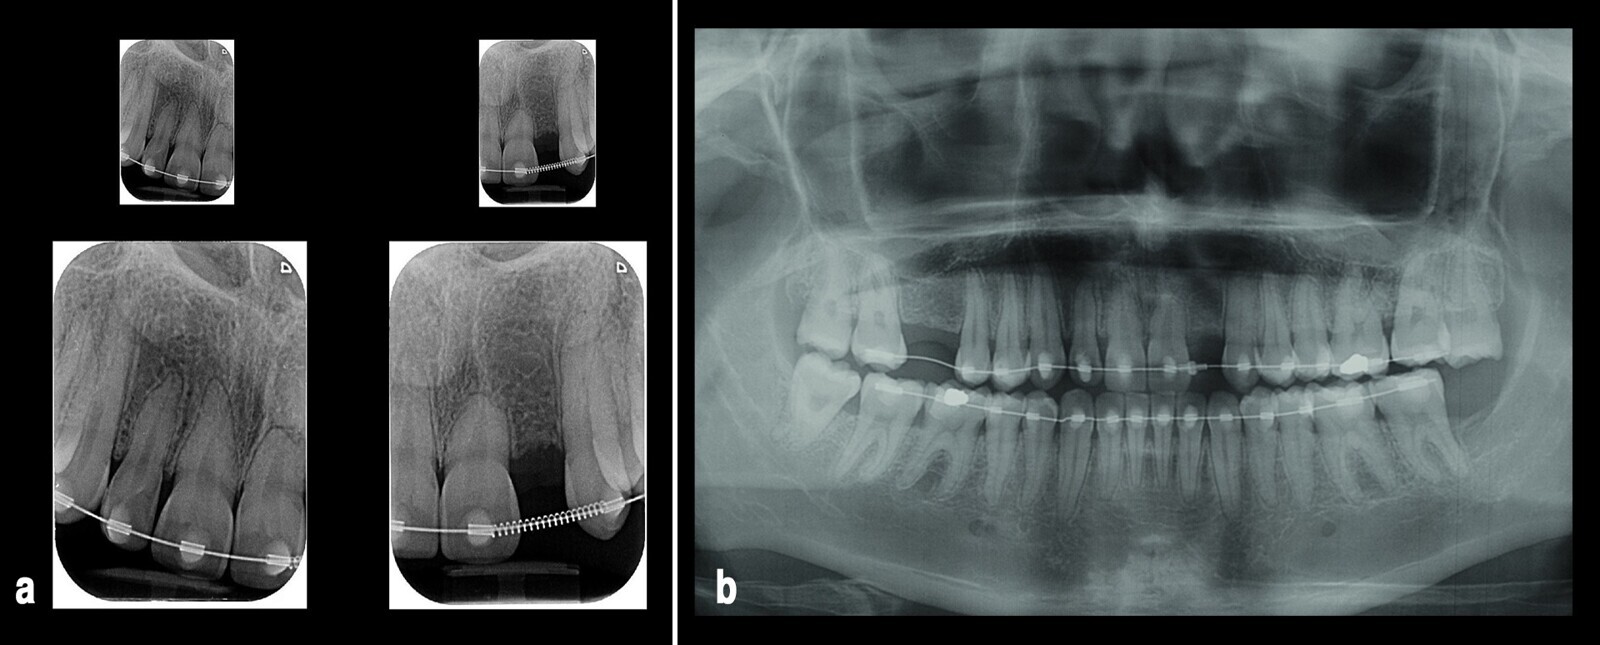

Logrados los objetivos de tratamiento se refiere el caso para estudio de rehabilitación oral con el fin de valorar el diámetro mesodistal del diente 22 previo al retiro de la aparatología. Después de comprobar que se tenía el espacio ideal para su posterior rehabilitación se finaliza el tratamiento con resultados aceptables, que solucionaron el motivo de la consulta de la paciente (Fig. 9).

Figura 9. El sistema de ortodoncia utilizado logró el espacio ideal para la posterior rehabilitación oral del diente 22 que se muestra en tres vistas (a, b, c). El tratamiento se finalizó con resultados aceptables con uso del retenedor, como se puede observar en tres proyecciones (d, e, f), tal como quería la paciente.